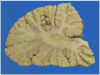

Context: Autopsy evaluation of the brain of a patient with frontotemporal dementia (FTD) can be daunting to the general pathologist. At some point in their training, most pathologists learn about Pick disease, and can recognize Pick bodies, the morphologic hallmark of Pick disease. Pick disease is a type of frontotemporal lobar degeneration (FTLD), the general category of pathologic process underlying most cases of FTD. The 2 major categories of pathologic FTLD are tauopathies (FTLD-tau) and ubiquitinopathies (FTLD-U). Pick disease is one of the FTLD-tau subtypes and is termed FTLD-tau (PiD).